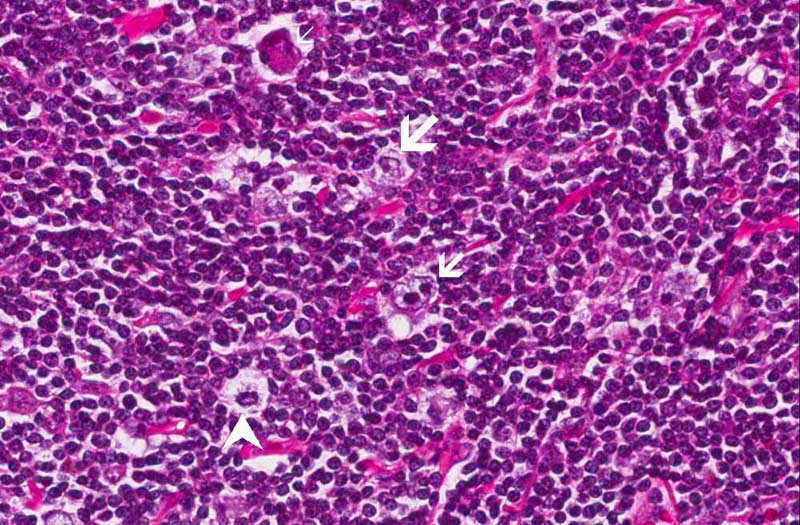

Area 1: Note that there are Reed-Sternberg cells (small arrow), Hodgkin cells (large arrow), lacunar cells (arrow head) which is diagnostic for nodular sclerosing classical Hodgkin lymphoma, and mummified cells (thin arrow).